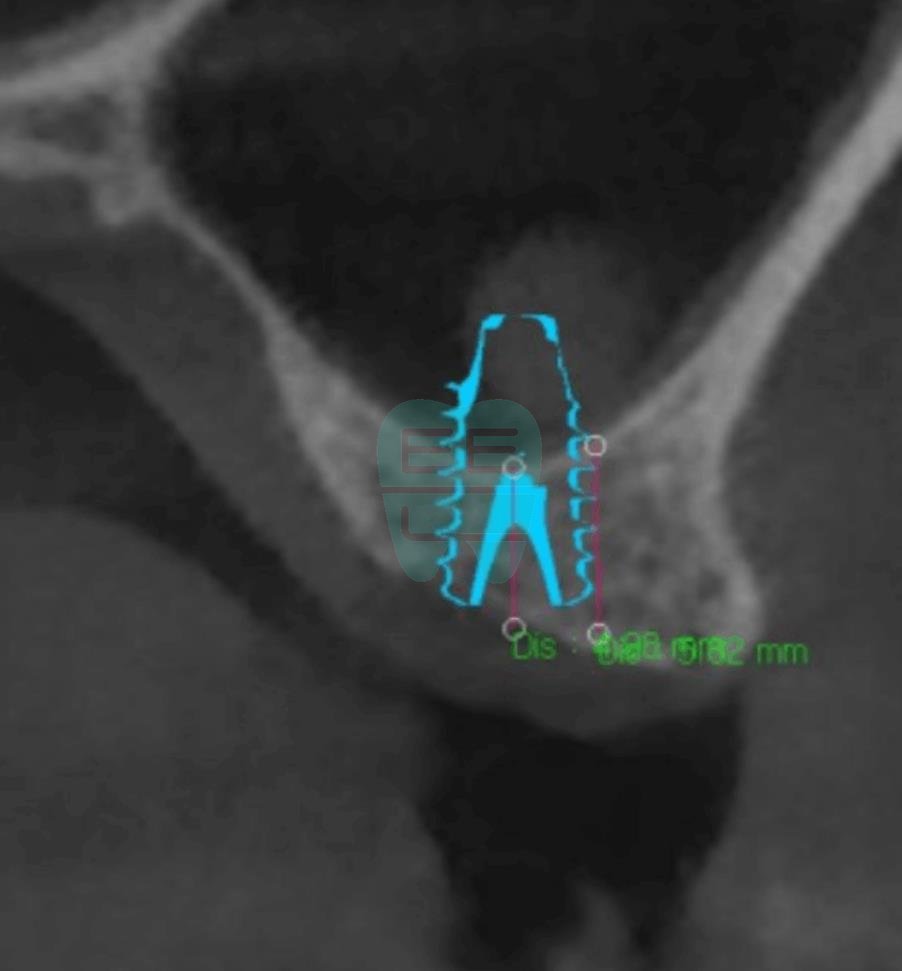

**Pre-operative CT Scan** — Insufficient bone height confirmed, sinus augmentation indicated.

**Post-operative CT Scan** — Maxillary sinus membrane safely elevated.